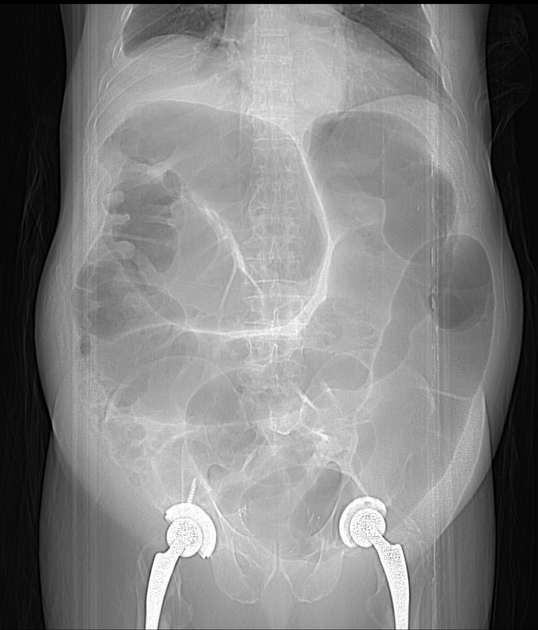

Paciente no PO de cirurgia ortopédica. HD?

A

Pseudobstrução Colônica (Síndrome de Ogilvie).

Distensão aguda do cólon por redução da atividade parassimpática do intestino grosso, leva à perda do peristaltismo colônico, frequentemente pós-operatório.

Mais comum em homens > 60 anos.

Ocorre em pacientes graves ou hospitalizados.